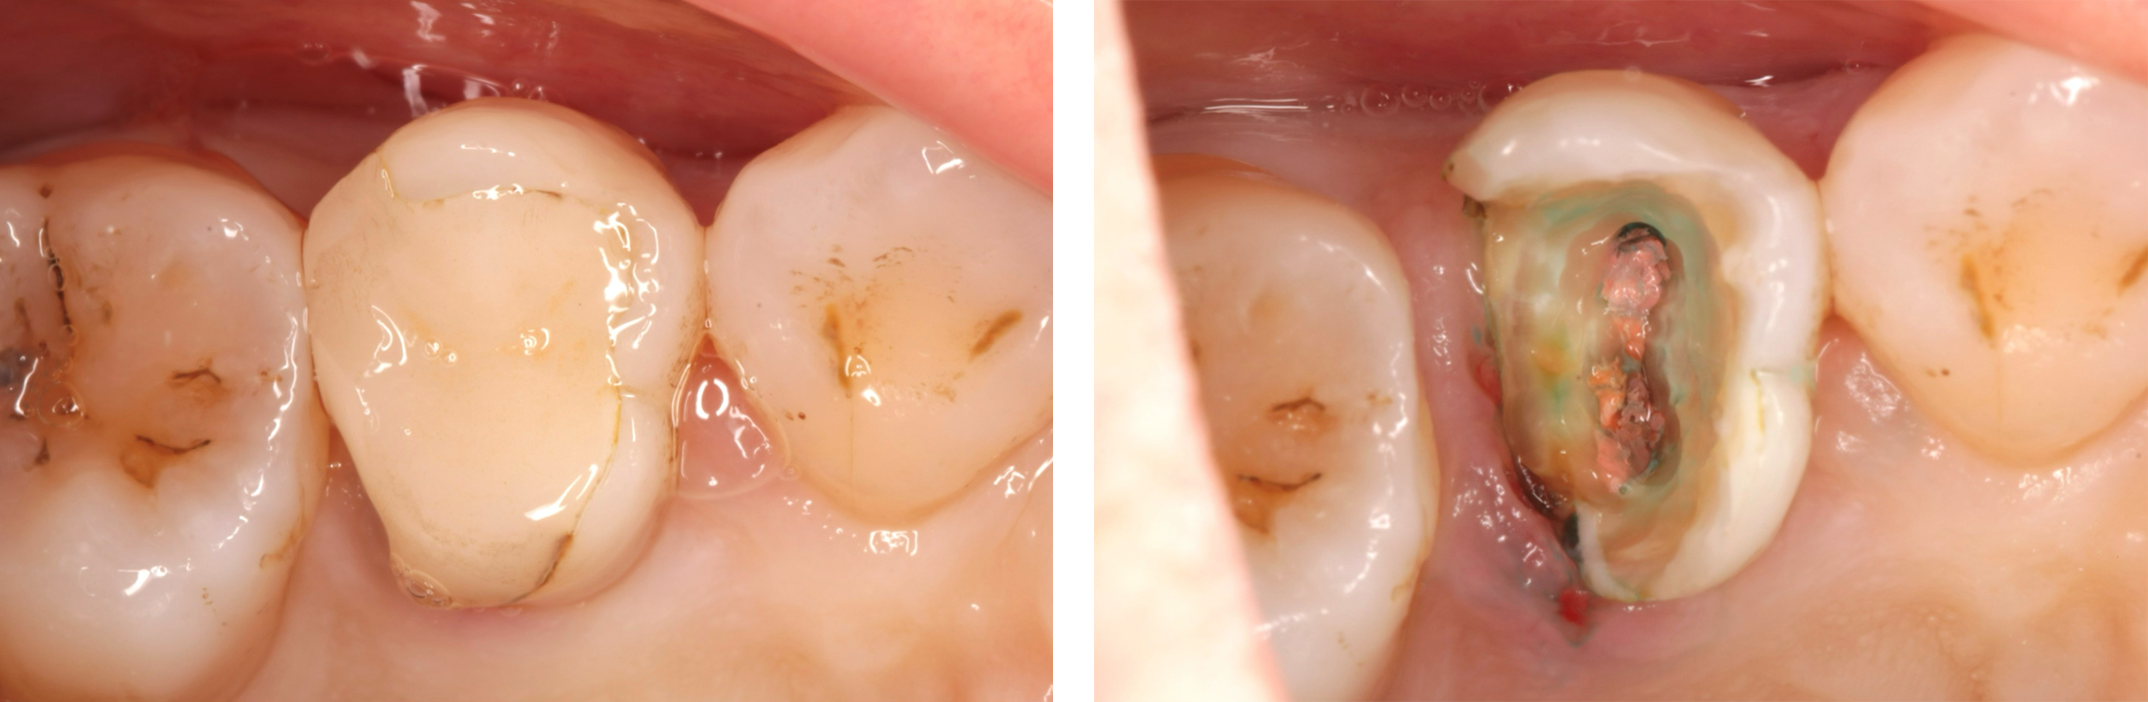

根管治療を行う際は、基本的に入っている詰め物や被せ物は一旦全て取り除いてから行います。被せ物(特に金属の被せ物)の下はX線画像では映らない虫歯が残っている可能性があり、それが原因で歯の中に細菌が入ってきている可能性があるので、それらを取り除く必要があります。

レントゲンでは明らかな虫歯が確認できないですが

はずしてみると、中は虫歯(薬液で青く染まる)で汚染されていて、根管の中まで感染していました。そしてそのう蝕を全て取り除き、根管に器具が入れられる必要最小限の穴を開けていきます(髄腔開拡)。